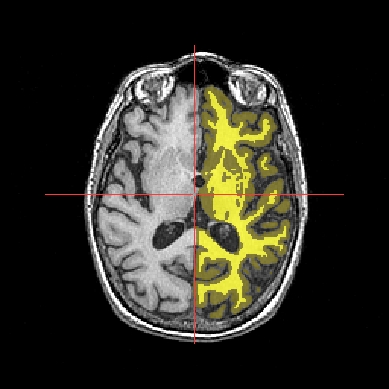

In the following example, 3 objects are loaded in Anatomist:

Object1 (O1): anatomy

Object2 (O2): regions of interest graph drawn from the anatomy. So these 2 objects are in the same referential.

Object3 (O3): nomenclature to associate colors to regions of interest according to their name. This object does not have to be put in a window. Link between names in the nomenclature and in regions of interest is done automatically by Anatomist.

These 2 objects are in the same coordinates system, so they will be placed in the same referential, that is to say they will have the same color circle (red by default).

Superimposing an anatomy and regions of interest¶